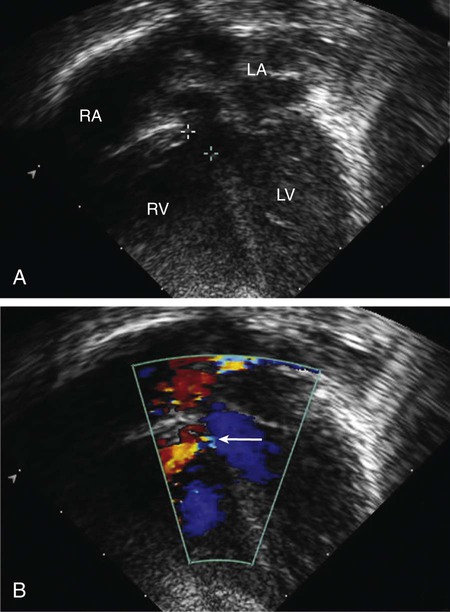

On echocardiogram, the cardiac chambers will be normal in size if the ductus is small. With large shunts, left atrial and left ventricular dimensions are increased. The ductus can easily be visualized directly and its size estimated. Color and pulsed Doppler examinations demonstrate systolic or diastolic (or both) retrograde turbulent flow in the pulmonary artery, and aortic retrograde flow in diastole (Fig. 426-10) in the presence of a large shunt.